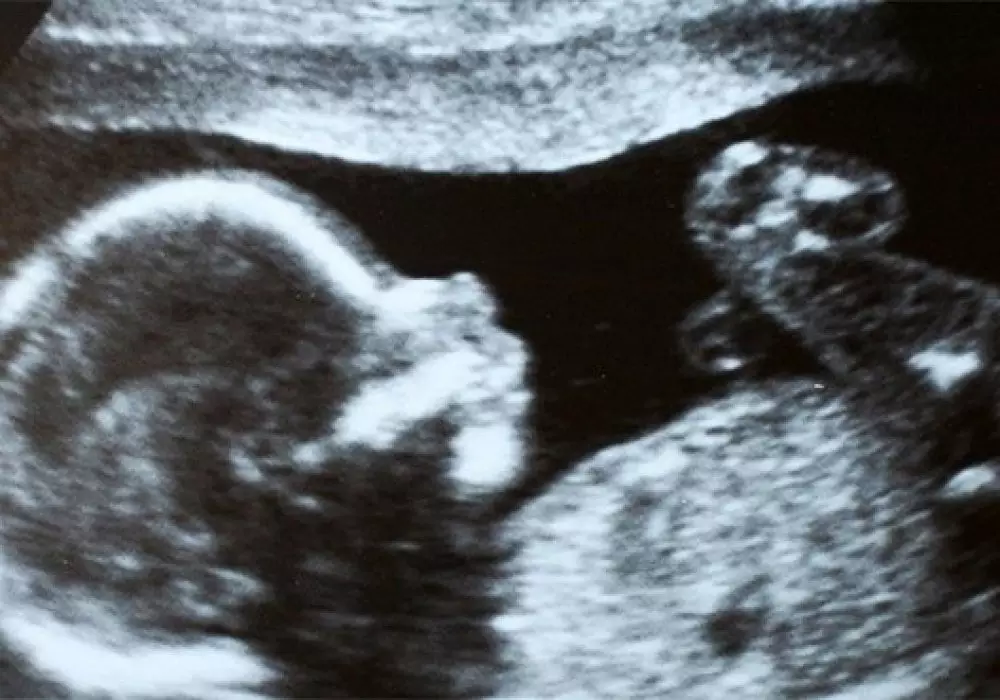

Чилийские врачи случайно обнаружили в утробе 92-летней женщины мумифицировавшийся плод возрастом 50 лет, сообщает РИА Новости. Пожилая пациентка обратилась в госпиталь Сан-Антонио с болями в животе после неудачного падения.

Врачи сделали рентген и выяснили, что внутри нее находится неродившийся плод с периодом вынашивания в 30 недель, он был зачат примерно 50 лет назад. Женщина не подозревала о своей беременности, а плод по неизвестным причинам погиб и мумифицировался, поэтому не создавал для чилийки особых проблем все эти годы. По итогам обследования врачами было принято решение оставить плод на месте, так как попытки извлечь его представляли бы опасность для престарелой женщины. Сейчас она чувствует себя лучше и переведена на домашнее лечение последствий полученной при падении травмы.